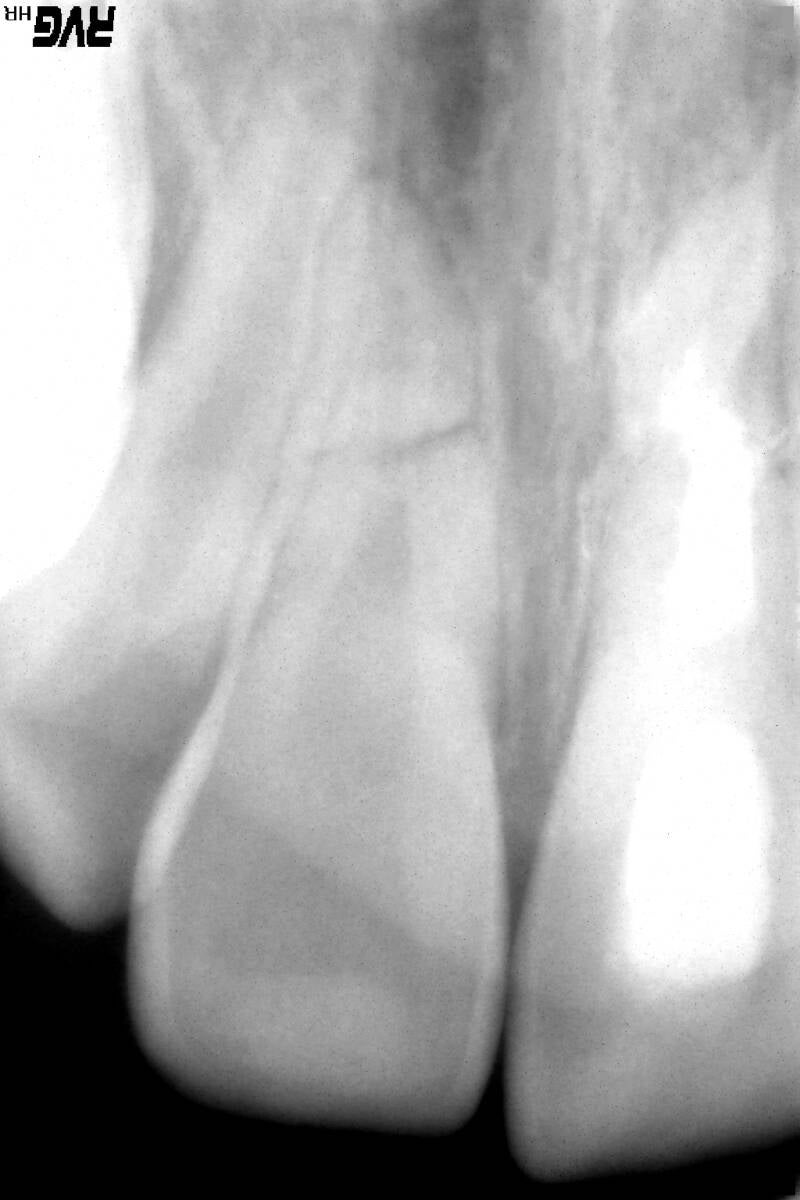

Op de röntgenfoto is de breuk van de wortels te zien.

De getransplanteerde hoektanden staan nu op de plek van de snijtanden.